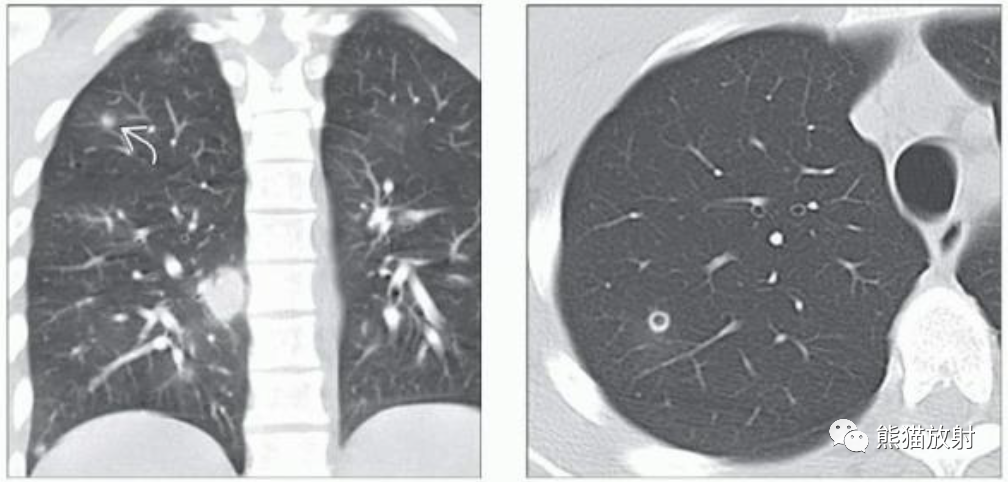

(左)26岁男性,患有急性髓细胞性白血病和中性粒细胞减少性发热。冠状NECT显示双肺多发结节,部分伴有磨玻璃影“晕征”。血清半乳甘露聚糖水平升高,推测诊断为侵袭性曲霉病,患者接受了2个月的伏立康唑治疗。

(右)同一患者治疗后,轴位NECT显示除右肺上叶小空洞结节外的所有病变均已消退。